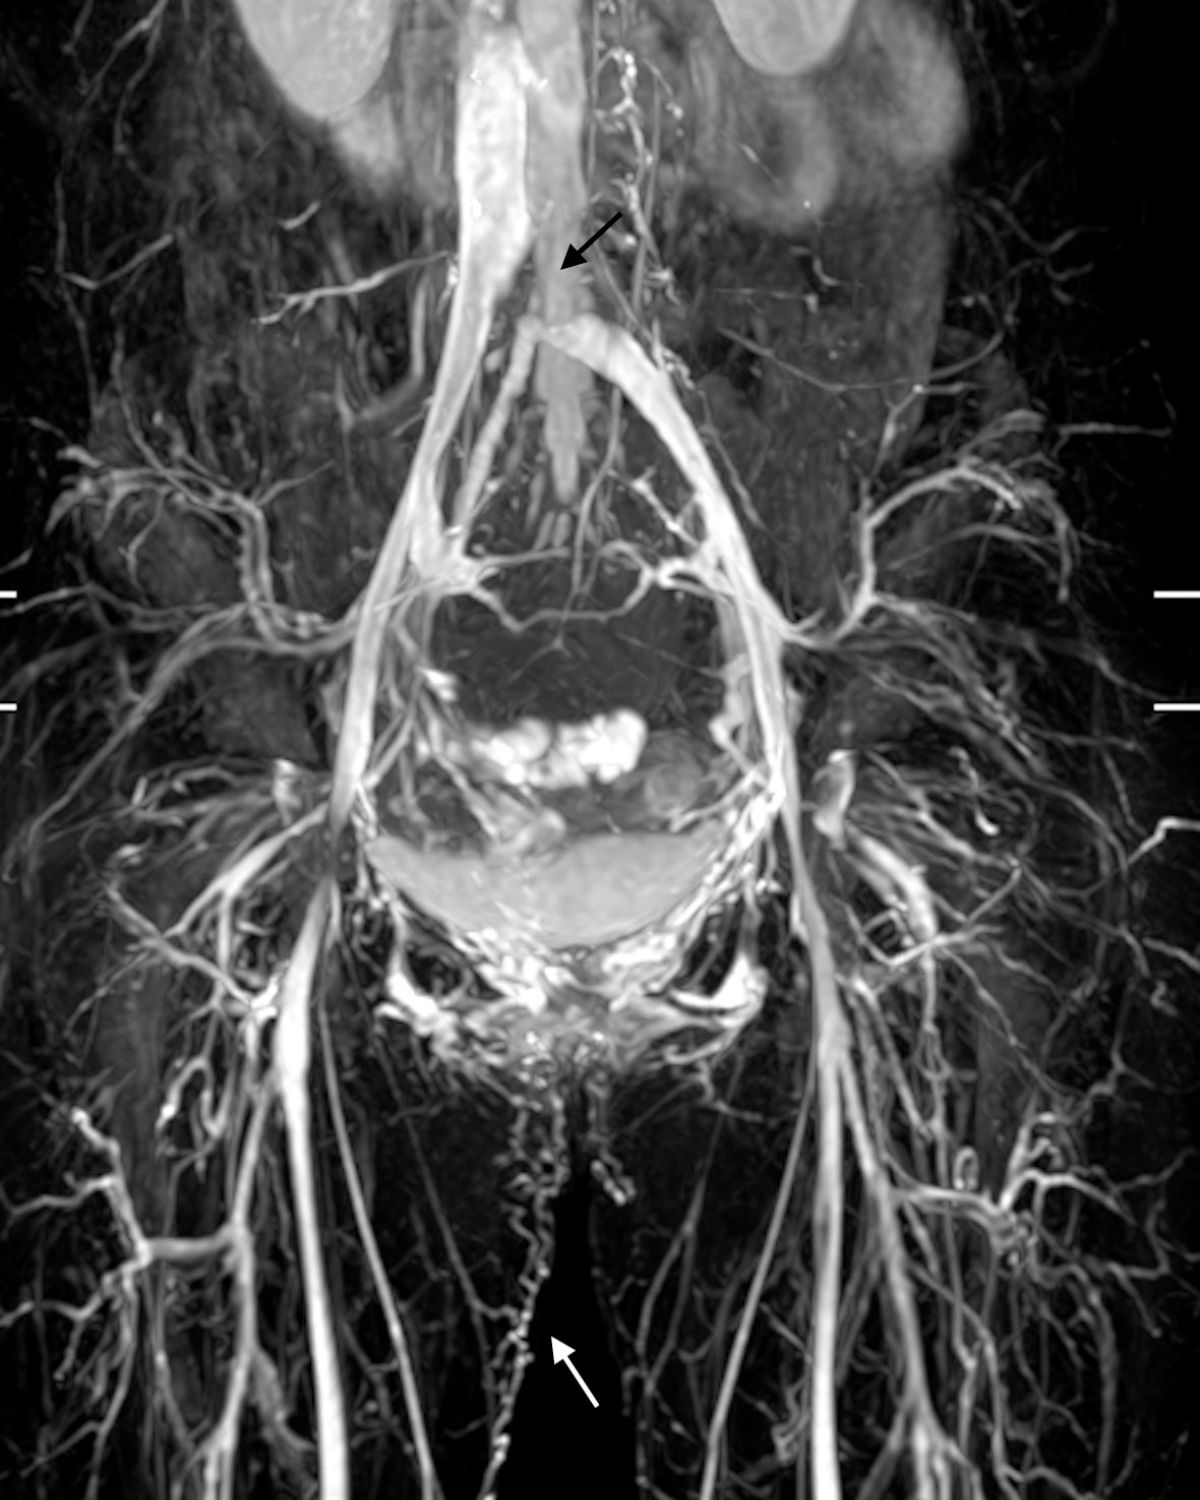

在狹小的骨盆腔內有各式各樣的器官擠在其中,當靜脈血流進入骨盆腔後(髂靜脈),走在腰椎骨和大動脈之間的狹小空間中,然後在身體的中線處左右會合。

當這個狹小空間變得更狹小(常見是腰椎骨退化或是動脈擴大)時,就會發生髂靜脈壓迫或阻塞。靜脈血流只能繞過狹窄點(由側肢循環)回到下腔靜脈。

圖四:

當靜脈血流變大時(如運動),來不及回心臟的血壓累積後,就會造成靜脈壓力高而造成足部和下腹的不適,甚至因為產生骨盆腔陰部滲漏,造成私密處腫脹不舒服。

這類的病人的靜脈曲張微創治療須要特別的小心。